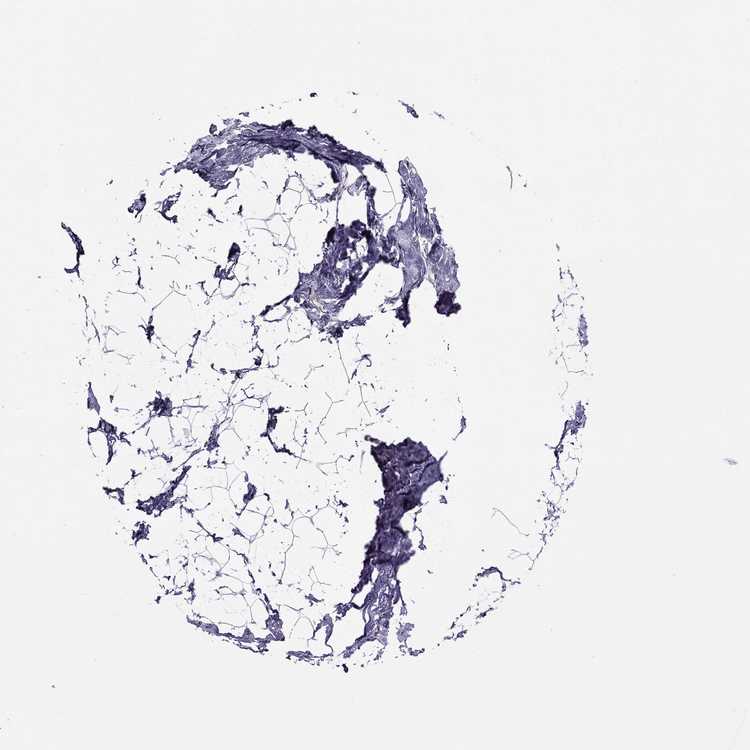

BREAST - Antibody stainingi

Antibody staining in the annotated cell types in the current human tissue is reported as not detected, low, medium, or high, based on conventional immunohistochemistry profiling in selected tissues. This score is based on the combination of the staining intensity and fraction of stained cells.

Each image is clickable and will lead to virtual microscopy that enables deeper exploration of all samples and also displays staining intensity scores, fraction scores and subcellular localization as well as patient and tissue information for each sample.

Antibody HPA018420

Adipocytes Not detected

Glandular cells Low

Myoepithelial cells Not detected